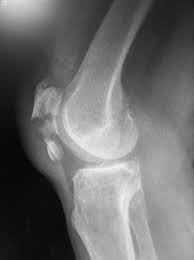

Knee X Ray Image. Skyline view of knee x ray is done to assess the patellofemoral joint alignment. Skyline views are done by flexing the knee keeping the detector perpendicular to the long axis of the limb.

The patella or kneecap is seen sitting in front and to the left of the femur. A lateral view x ray shows the knee from the side. The image here is a front to back view of the knee joint also called the ap view.